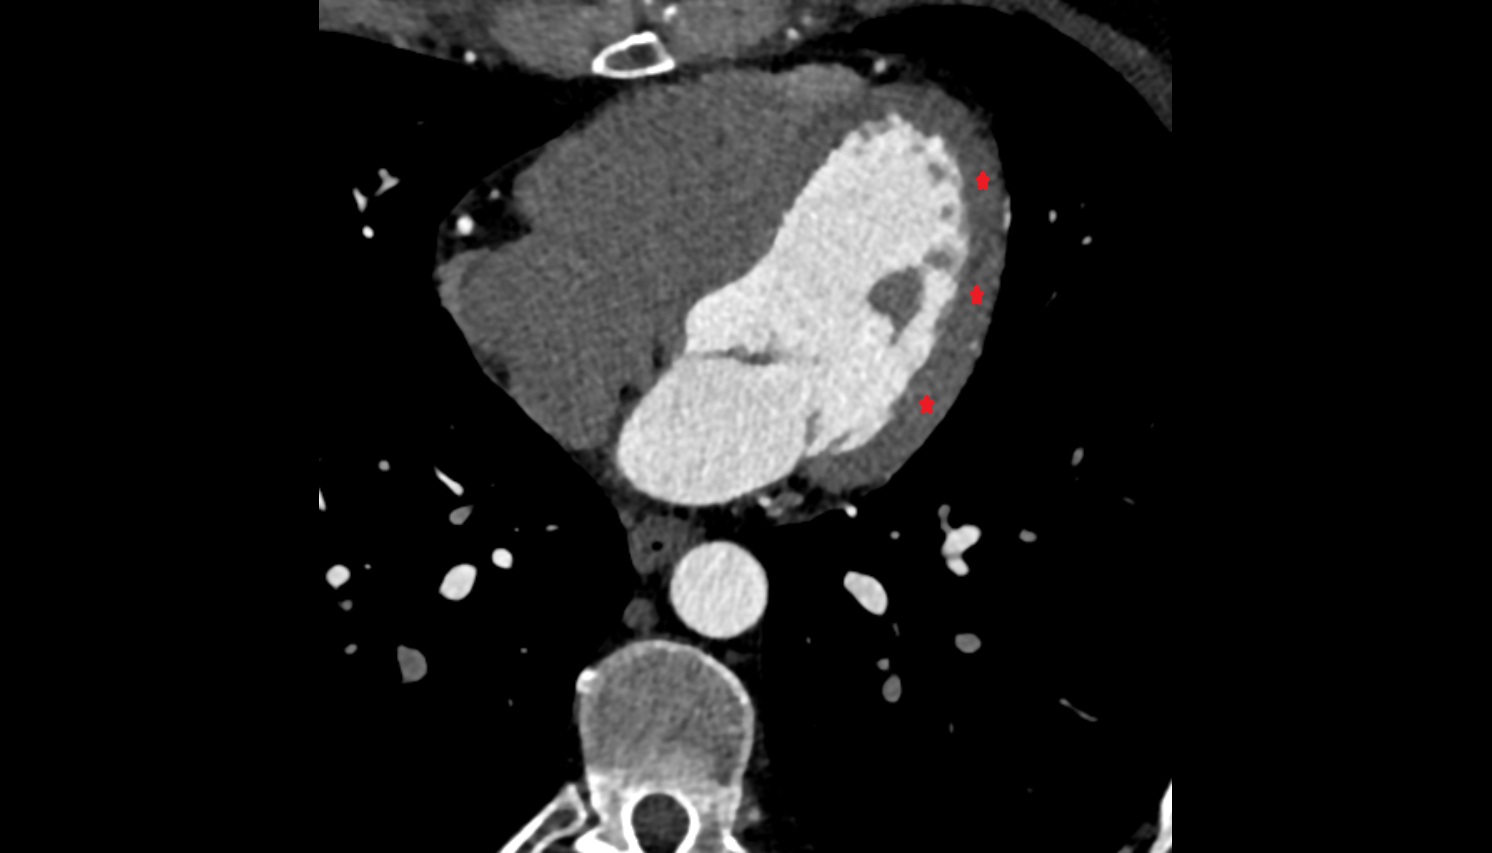

- Heart

- Left ventricle

- Right atrium

- Left atrium

- Right ventricle